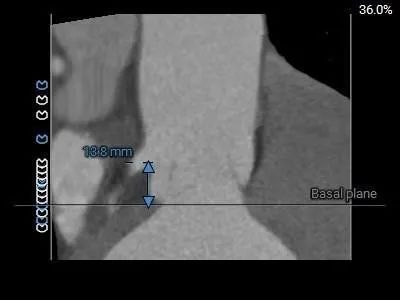

术前CT评估

三叶式主动脉瓣,LVOT敞口型,STJ、瓦氏窦内径可,升主动脉增宽

心室

左心室扩大

• 三叶式主动脉瓣,瓣叶无明显增厚,反流病例,无钙化分布,LVOT敞口型,主动脉瓣环约27.3mm,结合瓣上多平面分析预估瓣环及瓣上可提供锚定力,STJ可辅助锚定,反流病例假体瓣膜锚定难度偏大,注意防范瓣膜移位风险。